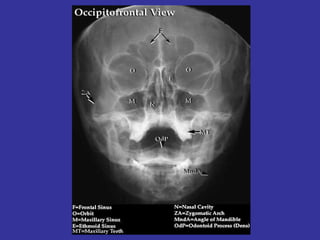

ANATOMY / DEVELOPMENT 4 Sinuses: Maxillary, Ethmoidal, Frontal, Sphenoidal MAXILLARY  SINUSES DEVELOPS  DURING  3rd & 4th GESTATIONAL  MONTH  WITH PNEUMATIZATION BETWEEN  BIRTH AND 12 MONTHS OF AGE ETHMOID   SINUSES DEVELOPS  DURING  3 rd  & 4 th  GESTATIONAL  MONTH. IS PRESENT AT BIRTH, DEVELOPING  UNTIL 12-14 YEARS OF AGE SPHENOID   SINUS DEVELOPED BY AGE 8-10 YEARS FRONTAL   SINUS DEVELOPS DURING  5 th  AND 6 th  YEAR.

In the sides of the nasal septum, there is 3 shelf-like structures where discharge is drain and is called  Turbinates  MAXILLARY ANT. ETHMOID  MIDDLE MEATUS FRONTAL POST. ETHMOID   SUPERIOR MEATUS SPHENOID LACRIMAL DUCTS   INFERIOR MEATUS (Largest and most visible)

Lab:   Transillumination of the maxillary and frontal sinuses Sinus X ray:  air-fluid level, complete opacity, mucosal thickening Waters-3 views Coronal CT:  demonstrate air fluids levels mucosal thickening, anatomical  variations suspected intracranial or orbital complication.  G.S. TX:   Amoxicillin  40-90 mg/kg/day Amoxicillin/potassium clavulanate  80-90 mg/kg/day Ceftriaxone  50 mg/kg/day  Erythromycin  50 mg/kg/day Omnicef  (cefdinir)  14 mg/kg/day Azythromycin  10/5  mg/kg/day Humidifier with Normal saline,  Mucolytics ( guaifenesin)  Topical nasal steroids,  Antihistamines (not recommended). Treat for up to 21 days or until free symptoms for 7 days